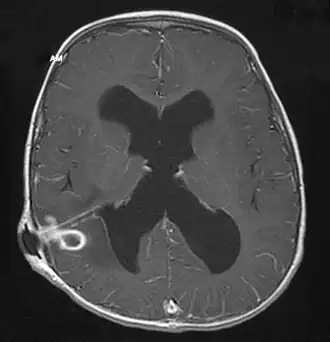

![]() Абсцесс головного мозга у пациента с вентрикулярным шунтом (МРТ с контрастным усилением). | |